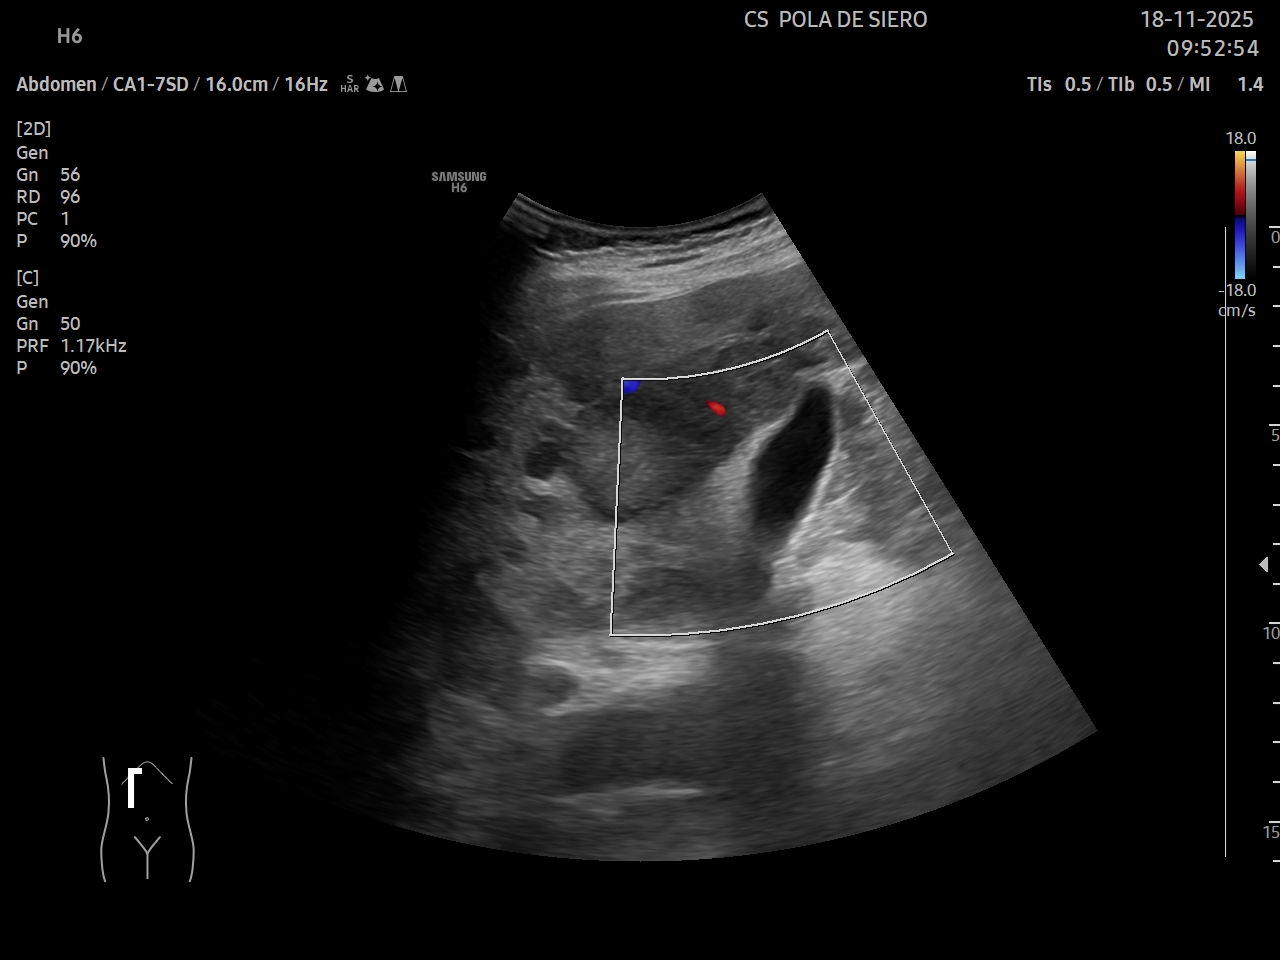

Ecografía clínica: múltiples imágenes hipoecoicas que afectan todo el parénquima hepático, vesícula alitiásica. Porta desplazada, permeable. Flujo hepatópeto y riñones normales. Bazo de tamaño normal. Vejiga no replecionada. No líquido libre.

Juicio clínico: metástasis hepáticas múltiples.